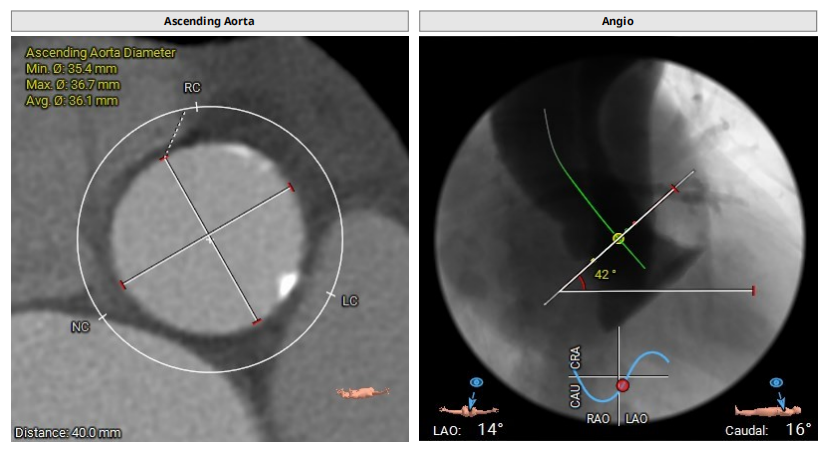

CT提示

主动脉根部:

三叶瓣,轻度钙化,法式窦结构尚可,左冠开口高度约15.3mm,右冠开口高度约17.1mm,STJ高度约22.6mm、直径约28.8mm,升主动脉未见明显扩张,心脏角度约42°,左室形态大小可,左冠切线位:LAO40° CRA9°,右窦居中位:LAO34° CRA3°,左右重叠位:LOA4° CAU23°。